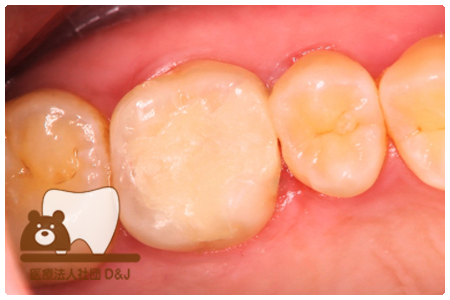

症例5フルジルコニアクラウン 右上6

治療前

治療後

46歳 女性

- 治療内容

- 虫歯を削った部分へフルジルコニアクラウンで修復を行いました。

- 治療期間

- 1カ月

- 費用

- 自費

フルジルコニアクラウン:77,000円(税込)

(R8.1月時点)

- その他の治療の費用は含まれておりません。

- リスク・副作用

- 強い力が加わると割れる可能性があります。また、噛み合わせや歯ぎしりの影響で脱離することがあります。